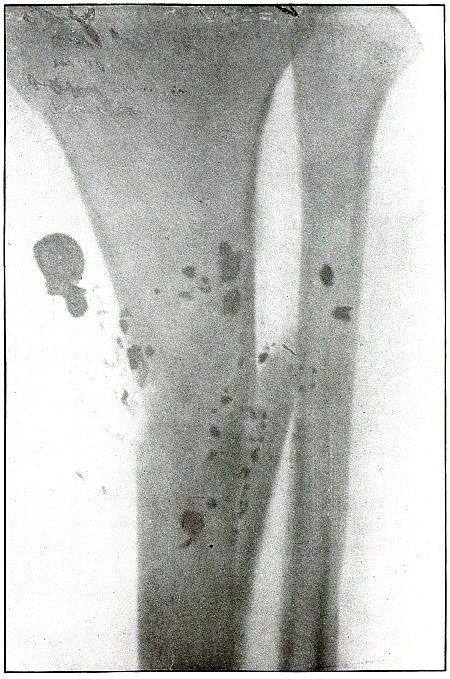

| 149. |

Gunshot wound, multiple, leg |

308 |